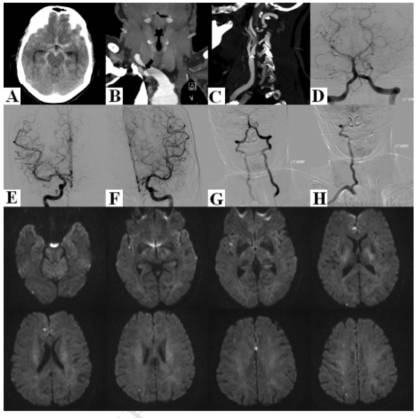

病例1:64岁女性患者,抽烟,既往高血压病史。因突发剧烈头痛入院,神经系统查体阴性。头颅CT提示颅底脑池内对称性、弥漫性SAH(图1A)。颈部CTA提示右侧锁骨下动脉近端重度狭窄,可见一钙化斑块起源于头臂干;此外,于右侧颈内动脉发现一钙化溃疡斑块(图1B和1C)。次日及1周后的DSA检查均未见颅内血管性病灶(图1D-F);右侧锁骨下动脉盗血明显,致使血流完全经右侧椎动脉逆转(图1G和1H)。第10天查MRI-DWI相上发现多发小梗死灶,分布于右侧大脑中动脉供血区和双侧扣带回(图1I-P)。患者诊断为右侧颈内动脉起源的颅内动脉血栓栓塞。给予阿司匹林口服后好转出院。

图1. A. 头颅CT显示弥漫对称的脑池SAH;B、C. 颈部血管CTA显示钙化的动脉粥样硬化斑块,导致右侧锁骨下动脉近端严重狭窄(B图箭头)和右侧颈内动脉起源处钙化溃疡斑块(C);D-H. DSA排除动脉瘤或血管畸形(D-F),DSA见右侧锁骨下动脉盗血现象,血流在右侧椎动脉逆流(G和H);最后2排MRI- DWI成像,显示右侧大脑中动脉供血区和双侧扣带回多发小弥散受限病灶。